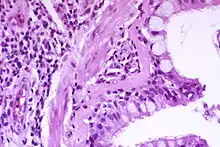

الفيزيولوجيا المرضية

{{مفصلة|مضمون=[[الفسيولوجيا المرضية للربو|الفيزيولوجيا المرضية للربو}} يحدثُ الربو نتيجةً للتهابٍ مزمنٍ في المنطقة الموصلة في السبيل التنفسي (خصوصًا الشعب الهوائية والقصيبات الرئيسية، مما يؤدي لاحقًا إلى زيادةِ قابليةِ انقباشِ العضلات الملساء المُحيطة، مما يؤدي مع عواملَ أُخرى إلى نوباتٍ من تضيقِ مجرى الهواء وحدوث الأعراض التقليدية للأزيز، وعادةً ما يكون هذا التضيق قابلًا للانعكاس مع أو بدونِ علاج. أحيانًا تتغير مجاري الهواء نفسُها.[24] تشملُ التغييرات النموذجية في مجاري الهواء زيادةً في الخلايا الحمضية وزيادةً في سُمكِ النسيج الضام الشبكي، وبشكلٍ مزمنٍ قد يزدادُ حجم عضلات المجاري الهوائية الملساء، مع زيادةٍ في عددِ الغدد المُخاطية. تشمل التغييراتِ خلايا أُخرى وهي الخلايا التائية والمتعادلة والبلعميات. قد يكونُ هناكَ مشاركةٌ من أجزاء الجهاز المناعي الأخرى والتي تشمل السيتوكين والكيموكين والهستامين واللوكوترايينات وغيرها.[23]